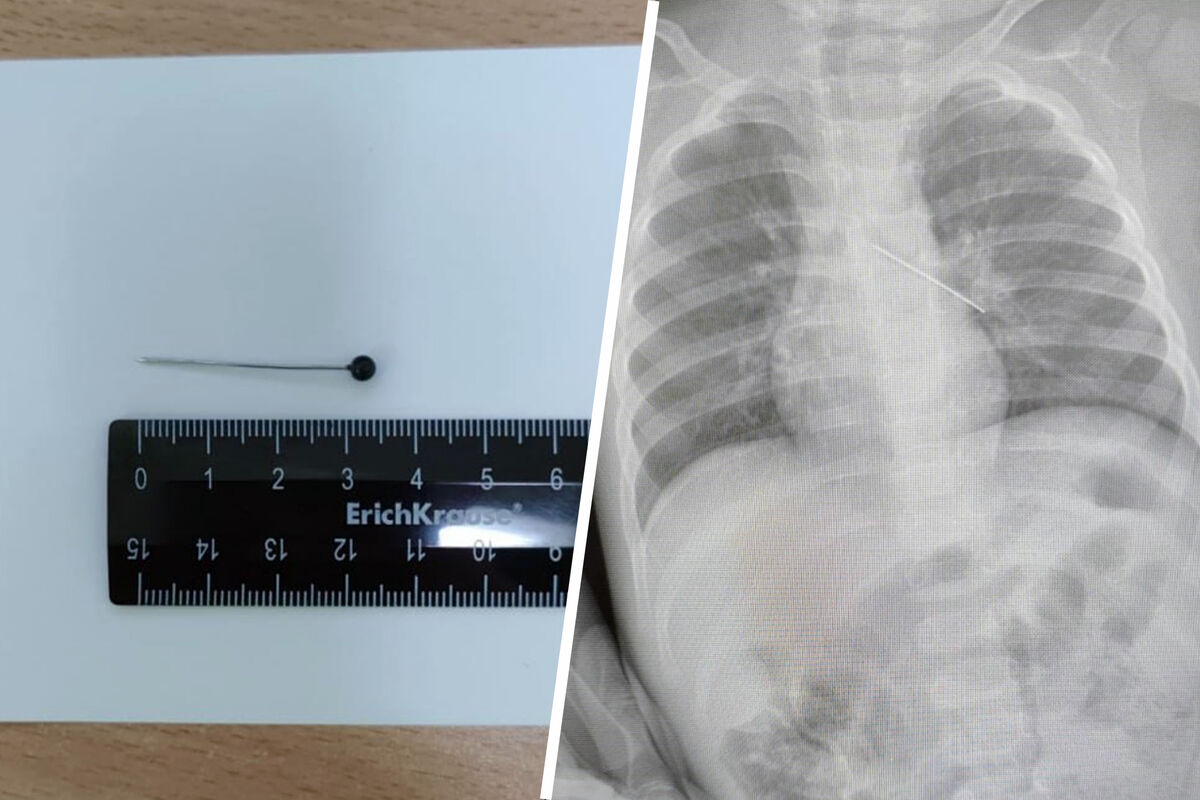

В ХМАО годовалый ребенок проглотил булавку

В Сургуте врачи спасли годовалого ребенка, проглотившего булавку

Врачи Центра охраны материнства и детства спасли 17-месячного ребенка, который из любопытства проглотил булавку. Об этом сообщила президент медицинского учреждения Лариса Белоцерковцева в Telegram-канале.

По словам медика, мать мальчика вовремя заметила беду и привезла ребенка в медицинское учреждение. Обследование показало, что инородный предмет зафиксировался в бронхах.

«Если бы бригада наших высокопрофессиональных специалистов не смогла удалить инородный предмет с помощью бронхоскопа, ребенка пришлось бы передавать торакальным хирургам для проведения большой операции», — пояснила Белоцерковцева.